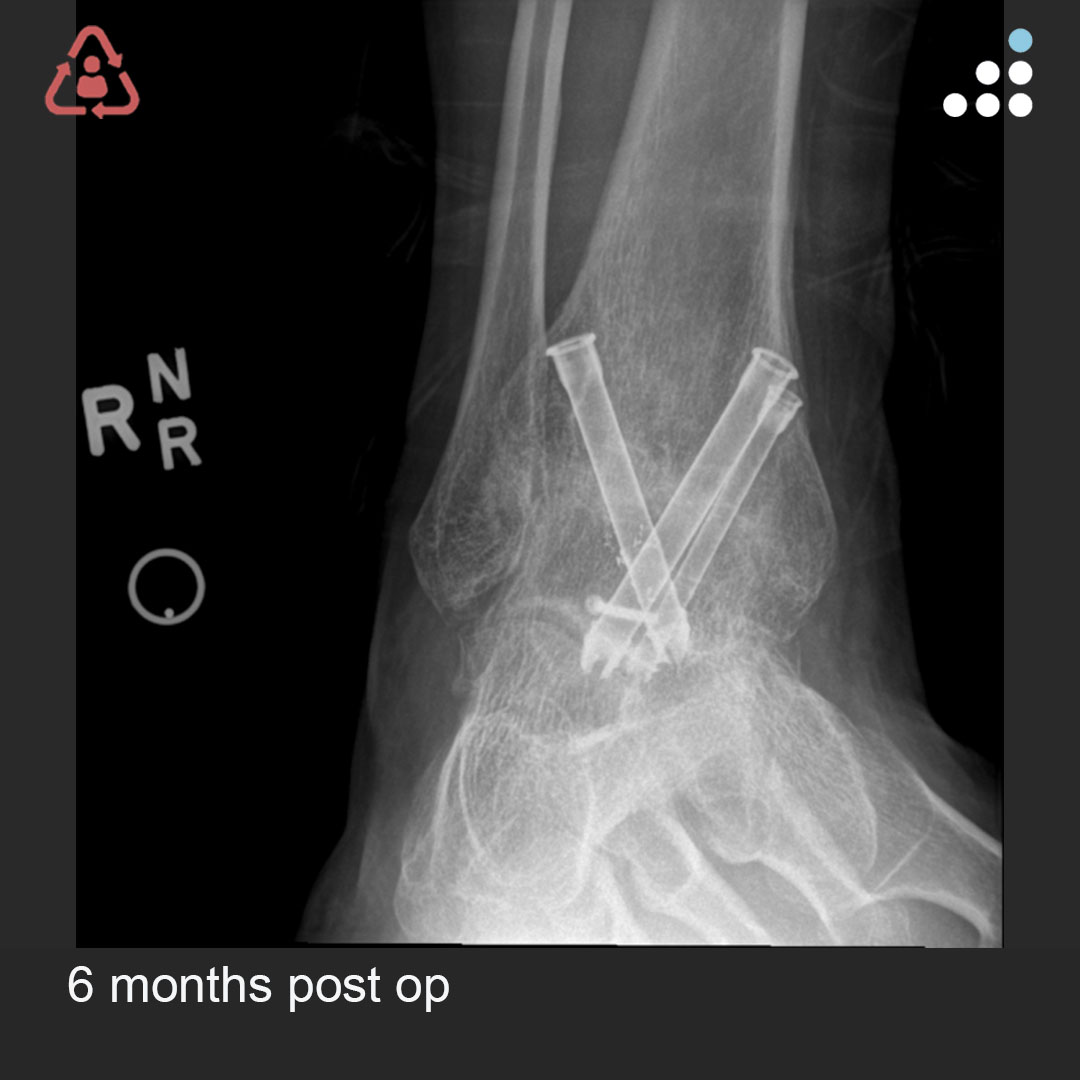

Here are intra-op & post-op images of yesterday's case by Dr. Jan Szatkowski(@orthotraumamd) & @IU_Health.

ANKLE PAIN 9 MONTHS S/P OPEN ANKLE FRACTURE-DISLOCATION IN 33M

Do you agree with the treatment? Why or why not?

Comment & keep the great conversation going!

#orthotwitter